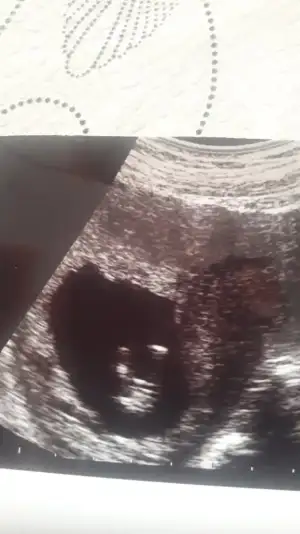

Merhaba tahmin ala bilirmiyim bacak arasi resmise var ?